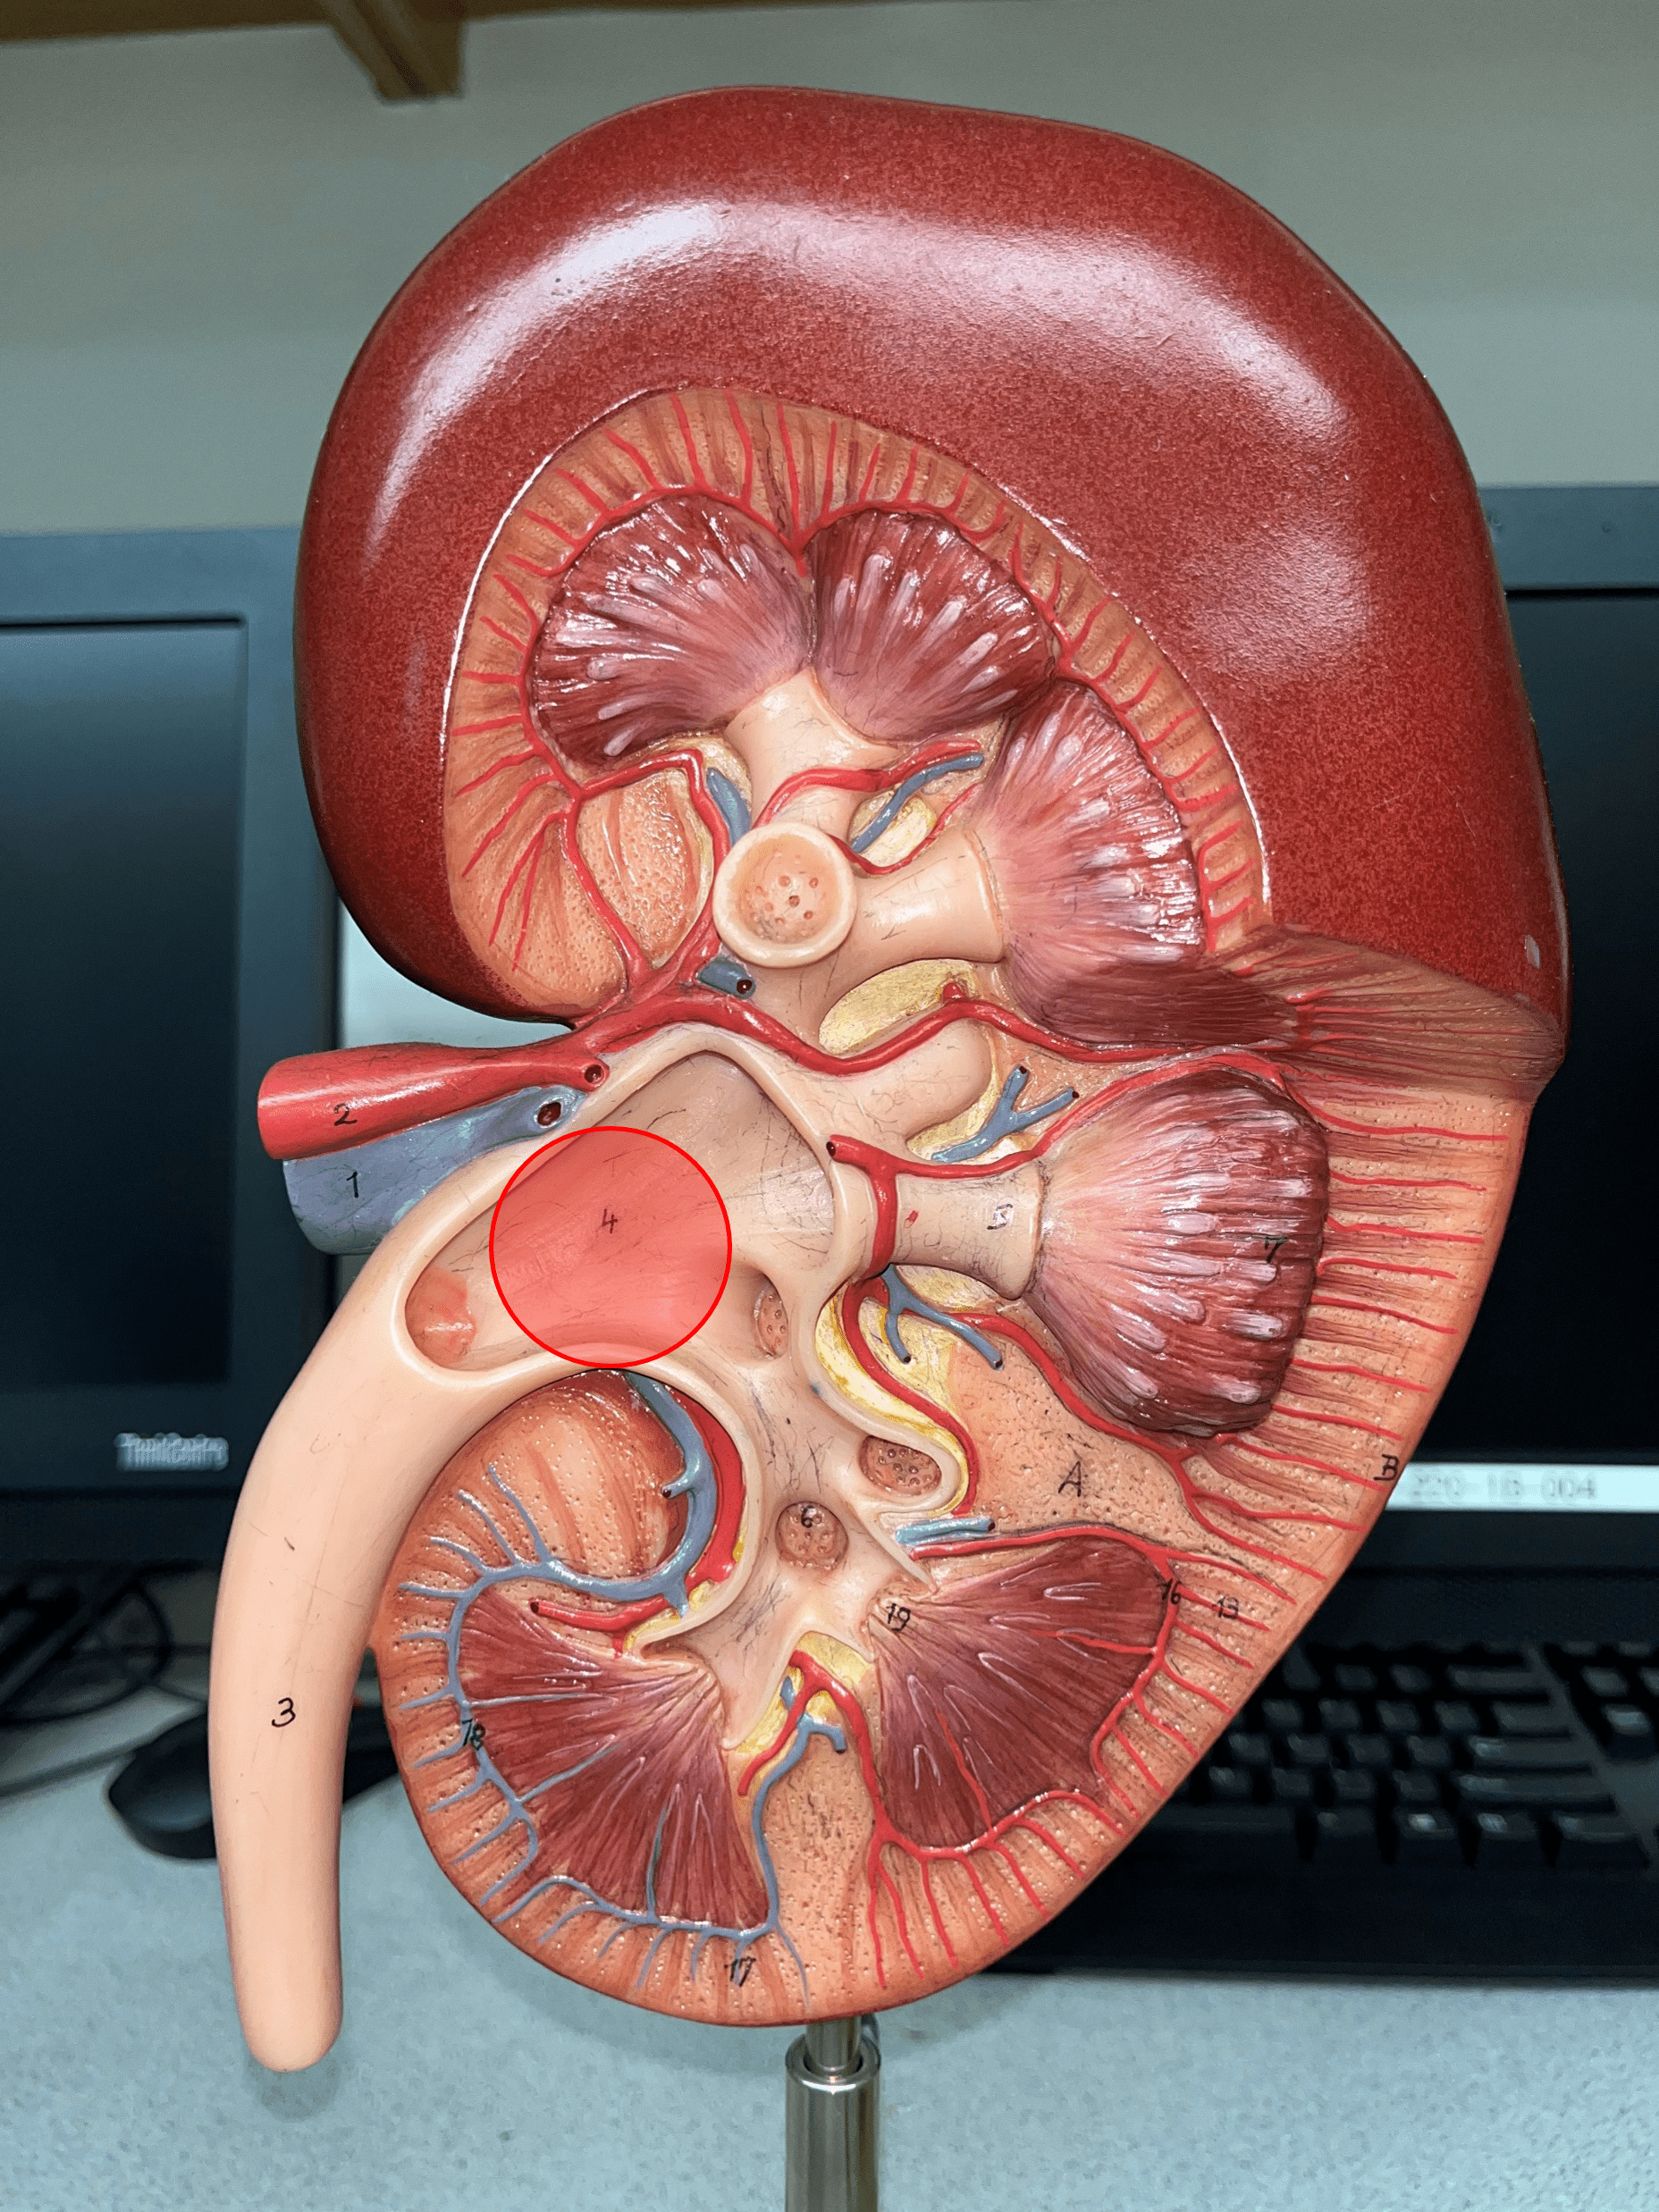

renal cortex

• The outermost region of the internal kidney.

• Superficial to the renal medulla.

• Appears slightly granular.

• Superficial to the renal medulla.

• Appears slightly granular.

renal pelvis

• The innermost region of the internal kidney.

• Collects urine from the major calyces and drains it into the ureters.

• Includes the minor and major calyces.

• Collects urine from the major calyces and drains it into the ureters.

• Includes the minor and major calyces.